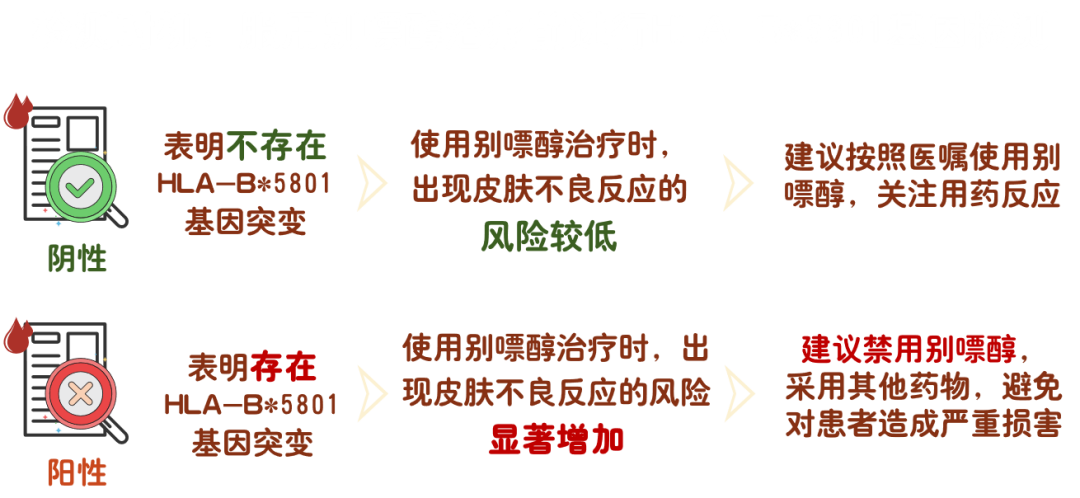

з ”з©¶еҸ‘жҳҺ пјҡ

HLA-B*5801 еҹәеӣ дёҺдәҡиЈ”дәәзҫӨжңҚз”ЁеҲ«еҳҢйҶҮеј•иө·зҡ„дёҘйҮҚзҡ®иӮӨдёҚиүҜеҸҚеә”жҳҫи‘—зӣёе…і�гҖӮ�гҖӮгҖӮгҖӮжңҚз”ЁеҲ«еҳҢйҶҮеҗҺжіӣиө·дёҘйҮҚдёҚиүҜеҸҚеә”зҡ„жӮЈиҖ…дёӯHLA-B*5801 еҹәеӣ жҗәеёҰзҺҮдёә 100%[3]�пјҢ�пјҢ�пјҢдё”дёӯеӣҪдәәзҫӨHLA-B*5801 еҹәеӣ йў‘зҺҮжҜ”е…¶д»–ең°еҢәдәәзҫӨйў‘зҺҮжӣҙй«ҳ�пјҢ�пјҢ�пјҢеҸҜиҫҫ 8%-20%[4]�гҖӮ�гҖӮгҖӮгҖӮз ”з©¶жҳҫзӨә�пјҢ�пјҢ�пјҢеңЁжңҚз”ЁеҲ«еҳҢйҶҮеүҚдёҫиЎҢ HLA-B*5801 еҹәеӣ жЈҖжөӢеҸҜжҳҫи‘—йҷҚдҪҺеҲ«еҳҢйҶҮеј•иө·зҡ„дёҘйҮҚзҡ®иӮӨдёҚиүҜеҸҚеә”зҡ„зҲҶеҸ‘зҺҮ�гҖӮ�гҖӮгҖӮгҖӮ